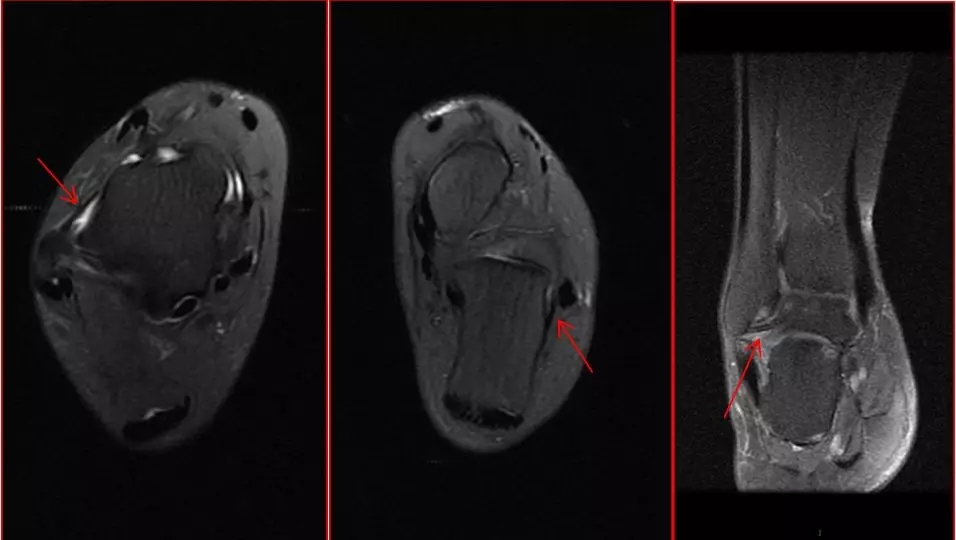

在我们医院的门急诊,常常会遇到主诉崴脚的病人,病人的病史或长或短。有的病人陈述崴脚以后,一两年内再出现多次崴脚(习惯性崴脚),病人均有踝关节肿胀、疼痛,经X线检查以后,均没有发现确切骨折,医生仔细检查后会让患者进行核磁检查,看看韧带是否有问题。很多患者非常不理解,就是一个小小的崴脚,为什么要做核磁检查?是不是医生小题大做了?骨头都没事,韧带就是有事也无碍大局。其实患者的这些观点都是错误的,崴脚并没有这么简单。 崴脚很常见 崴脚,是踝关节扭伤的俗称,指踝关节受到剧烈扭转,使关节周围的韧带、肌肉等出现损伤,为低能量损伤,不同于车祸、坠落伤等造成严重骨折脱位的高能量损伤。踝关节扭伤在日常生活中非常常见,是医院门急诊骨科最常见的损伤,占整个运动损伤的15%,其中85%为外侧韧带损伤。扭伤可发生于任何年龄,以年轻人群多见,据文献报道,在美国,每天有23000例踝关节韧带损伤。踝关节扭伤后大多数人可以康复,但15%-20%的运动损伤患者可能存在持续性疼痛,影响工作和生活。日常生活中发生踝关节扭伤的原因较多:如下楼梯落空、道路凹凸不平等;某些体育活动也常常发生崴脚,最容易发生于剧烈的体育运动包括:篮球、羽毛球、足球、网球等;穿高跟鞋的女士也易出现踝关节扭伤。 及时治疗很重要 踝关节扭伤后容易被忽视而延误治疗。其延误治疗的原因有很多,许多人(包括中小型医院的某些医生)认为,没有骨折的踝关节软组织挫伤是“小事一桩”而不被重视;患者的临床依从性不高,认为做核磁检查意义不大,就算是韧带损伤也没什么大事,易造成治疗不及时或治疗不当;一些运动员,因为踝关节的轻、中度扭伤,没有及时治疗和康复,从而影响运动成绩而退役;普通人因为扭伤治疗不当,导致踝关节肌力不足、运动能力下降、运动区域降低、不稳定(10-30%),容易反复扭伤,造成踝关节功能障碍,长期被疼痛和肿胀困扰。 了解一下踝关节 踝关节是人体重要的承重关节,可进行背伸、跖屈、内旋、外旋等多种多样的复杂活动,是足部主要的活动枢纽。其解剖结构就像人骑在马上,马是距骨,支撑着上面的人,也就是小腿,人的两只脚是内踝和外踝,周围的韧带则是马镫及马鞍,骑马者的稳定性取决于马镫及马鞍的牢固程度,所以踝关节的稳定性取决于这些韧带。 踝关节稳定由三套韧带构成:内侧韧带(又称三角韧带)复合体(胫舟韧带、胫跟韧带、胫距前韧带、胫距后韧带)、外侧韧带复合体(距腓前韧带、跟腓韧带、距腓后韧带)、下胫腓韧带复合体(下胫腓前韧带、下胫腓横韧带、下胫腓后韧带、骨间韧带)。外踝比内踝低,两者相差约1.5cm,内翻幅度约35°-41°,外翻幅度约22°-25°。 崴脚伤到的那些韧带 踝关节扭伤分为内翻位、外翻位损伤,以跖屈内翻位损伤最多见。跖屈内翻位扭伤多造成外侧副韧带损伤,其中距腓前韧带较薄,在跖屈内翻的情况下,被拉的最长,遭受张力最大,最容易损伤;跟腓韧带为唯一的踝关节囊外韧带,内翻力过大时也会发生损伤,距腓后韧带在三根韧带中是最强的,其走行与水平面平行,损伤最少见。外翻位扭伤多损伤内侧韧带复合体,它起自内踝,呈扇形向下,止于舟骨、距骨和跟骨,为踝关节最坚强的韧带,不易断裂,而是常常发生内踝的撕脱骨折。下胫腓韧带复合体损伤则为高位踝扭伤所致。 崴脚得查核磁的原因 患者扭伤后到医院就诊,X线平片为首选检查方法,观察有无骨折脱位,但是对于韧带损伤无法显示。核磁共振对软组织损伤有高分辨率、多序列、多平面成像、无辐射、评价快速等优点,成为骨关节系统韧带及软组织损伤的重要检查方法。根据损伤程度,韧带损伤可分为I-IV度损伤:I、II度损伤较轻,为韧带纤维轻度撕裂伤,可以保守治疗,III度损伤为韧带纤维大部分断裂,IV度损伤为韧带完全断裂,III、IV度损伤会造成关节失稳,经保守治疗效果不明显的,应该考虑手术治疗。 上图为距腓前韧带III度及IV度损伤 当今生活中越来越多的人群喜欢运动、旅游,增加了踝关节扭伤发生的频率。希望大家对踝关节扭伤加以重视,有针对性地及时治疗,避免韧带及软骨的损伤形成踝关节长期疼痛、肿胀,从而达到加速康复、提高生活质量和幸福指数的目的。 拥有健康足踝,生活更加美好! 作者简介 赵晖 主任医师 天津市天津医院天津大学天津医院放射一科 中华医学会天津市放射学会肌骨专业委员会委员 中国研究型医院学会肿瘤影像诊断学专业委员会骨骼软组织影像学组委员 中国中西医结合学会第四届骨伤科专业委员会委员 中国医药教育协会肩肘运动医学规范化培训冬季运动损伤分会委员 中华医学会天津市心身医学会风湿免疫学组委员 中华医学会影像技术分会第八届骨密度影像技术专业委员会QCT学组委员 延伸阅读